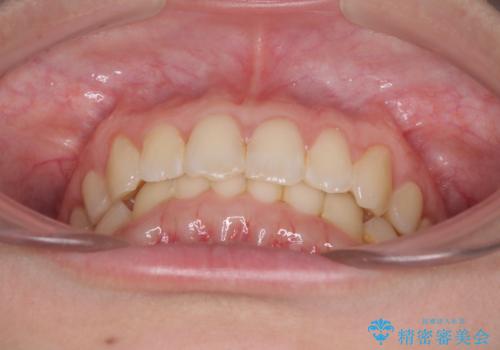

インビザラインによる前歯の矯正治療

- 口元の深い咬み合わせ(ディープバイト)を気にして来院された患者様です。

インビザラインによる上下歯列の遠心移動(後方移動)により、口元のデコボコとディープバイトを改善することとしました。

下顎左右の犬歯とその後ろにある第一小臼歯、計4歯がシミュレーション通りに動かずディープバイトがなかなか改善されませんでした。

マウスピースの再製作を何度か行いましたがうまくいかないため、部分的にワイヤー矯正を併用することを提案しました。しかし、最も気になっていた前歯のデコボコはきれいに改善されたため、これ以上治療を希望されず、治療を終了することとしました。(今後気になった際には再開する予定です)